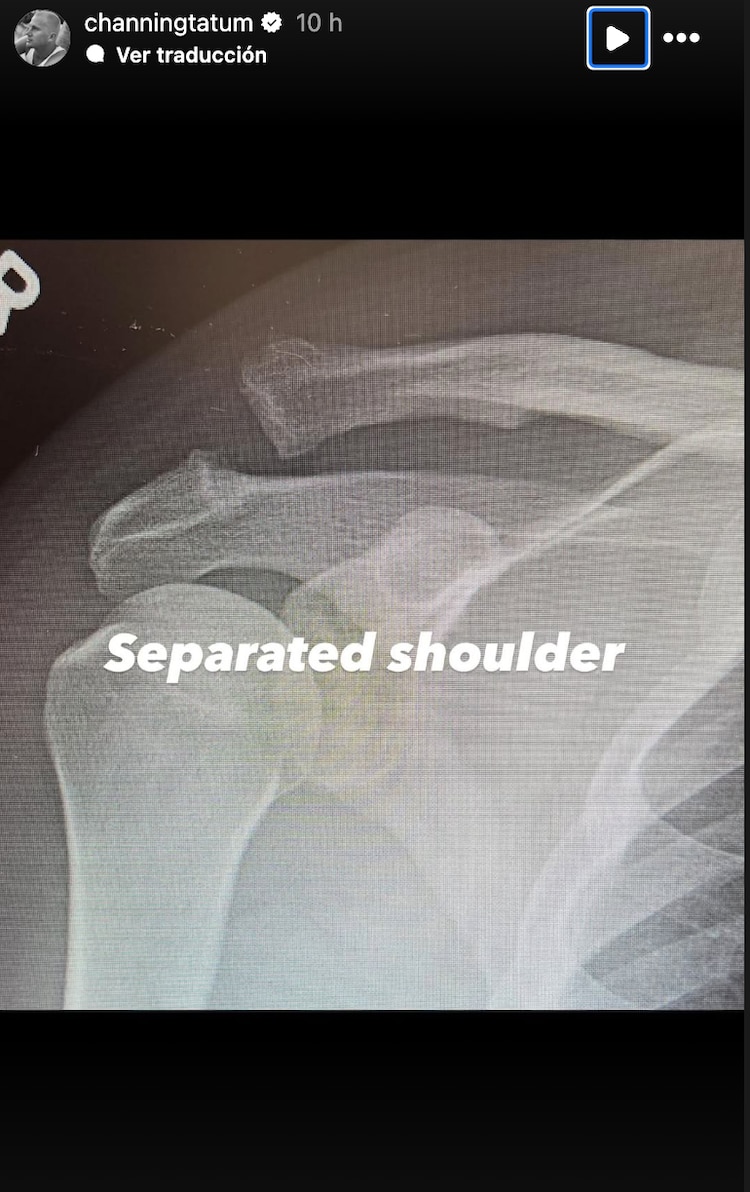

El actor Channing Tatum fue hospitalizado y operado del hombro, él tenía la extremidad separada y se sometió a una cirugía para ello.

La estrella de “Step up: camino a la fama” publicó unas imágenes en sus historias de Instagram en las que mostró las radiografías de cómo tenía el hombro separado.

Posteriormente en otra fotografía compartió cómo le quedó el hombro tras haberse sometido a la cirugía, pues en la radiografía se le puede ver que le colocaron un clavo en la extremidad.